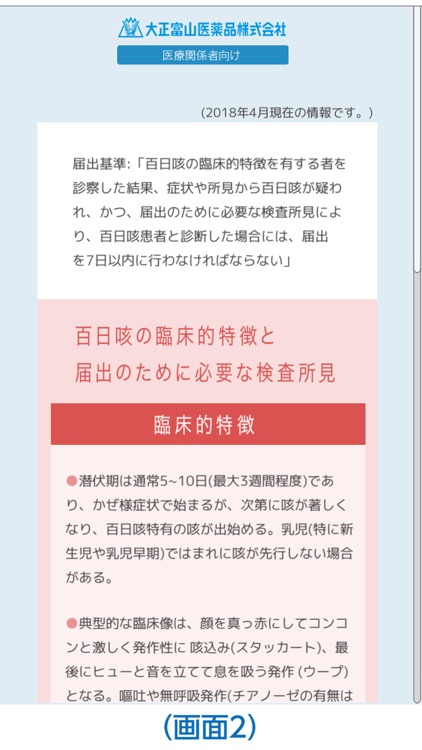

②各疾患の診断・治療において参考となる情報をすぐに参照できます。(画面2)